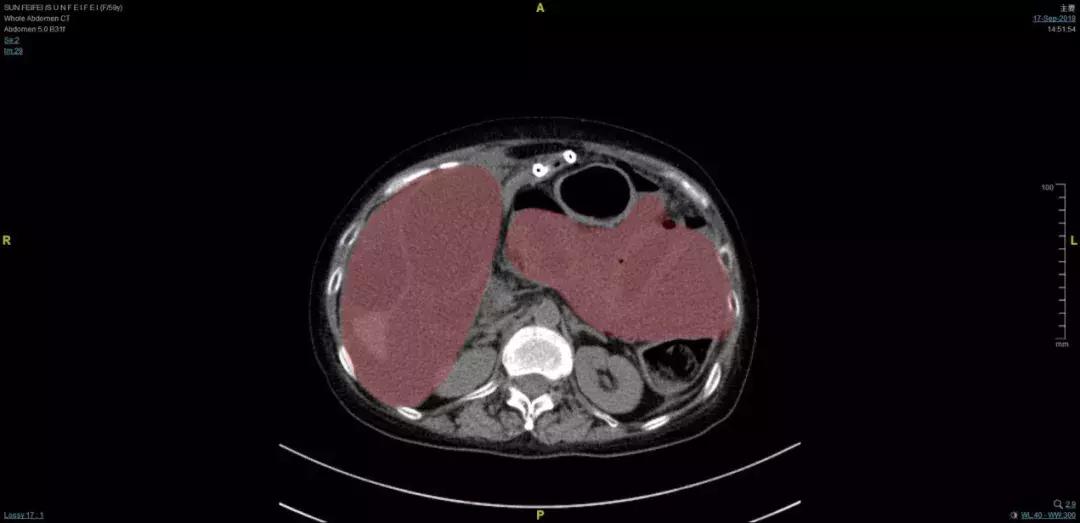

患者腹腔增强CT,红色部分均为粪液

情况危急,急诊科进行紧急生命支持后迅速请腹膜后肿瘤外科会诊,在拿到腹部增强CT和穿刺结果后,罗成华主任和苗成利副主任医师发现,由于肠道破裂,王女士的腹腔内充满了粪液,结合患者晚期苗勒氏管肉瘤的病史,手术治疗迫在眉睫!